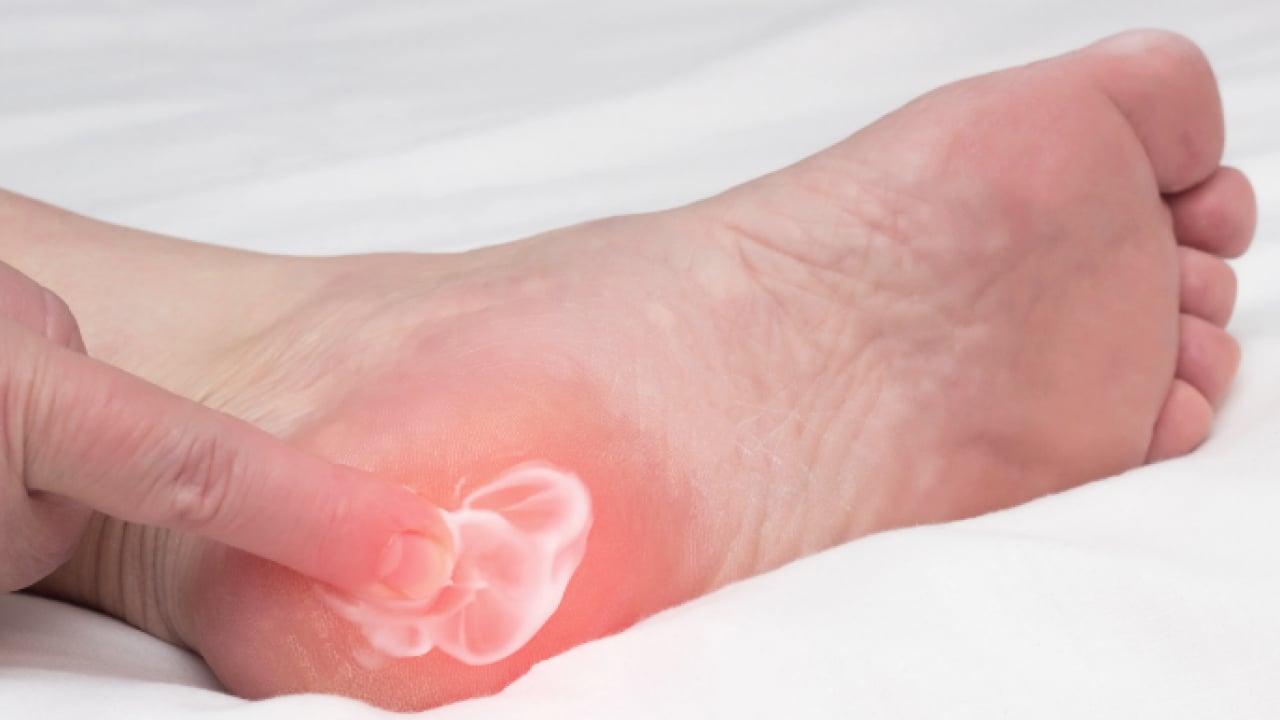

Hastaneden yapılan açıklamaya göre, topuk ağrısı, özellikle uzun süre ayakta kalan kişilerde yaşam kalitesini ciddi şekilde düşüren yaygın sorunlardan biri olarak öne çıkıyor. İstirahat, tabanlık, iğne ve fizik tedavi gibi yöntemlere rağmen geçmeyen topuk dikeni vakalarında yeni bir tedavi yaklaşımı hastalara umut oluyor.

Açıklamada görüşlerine yer verilen Prof. Dr. Tümay Bekci, topuk dikeninin, ayak tabanında yer alan ve topuk kemiğine yapışan bağ dokusunun iltihaplanmasıyla ortaya çıktığını aktardı.

Travma, aşırı yüklenme ve uzun süre ayakta kalma gibi faktörlerin süreci tetiklediğine değinen Bekci, tedavi edilmediğinde ise hastalığın kronikleşebildiğini ifade etti.